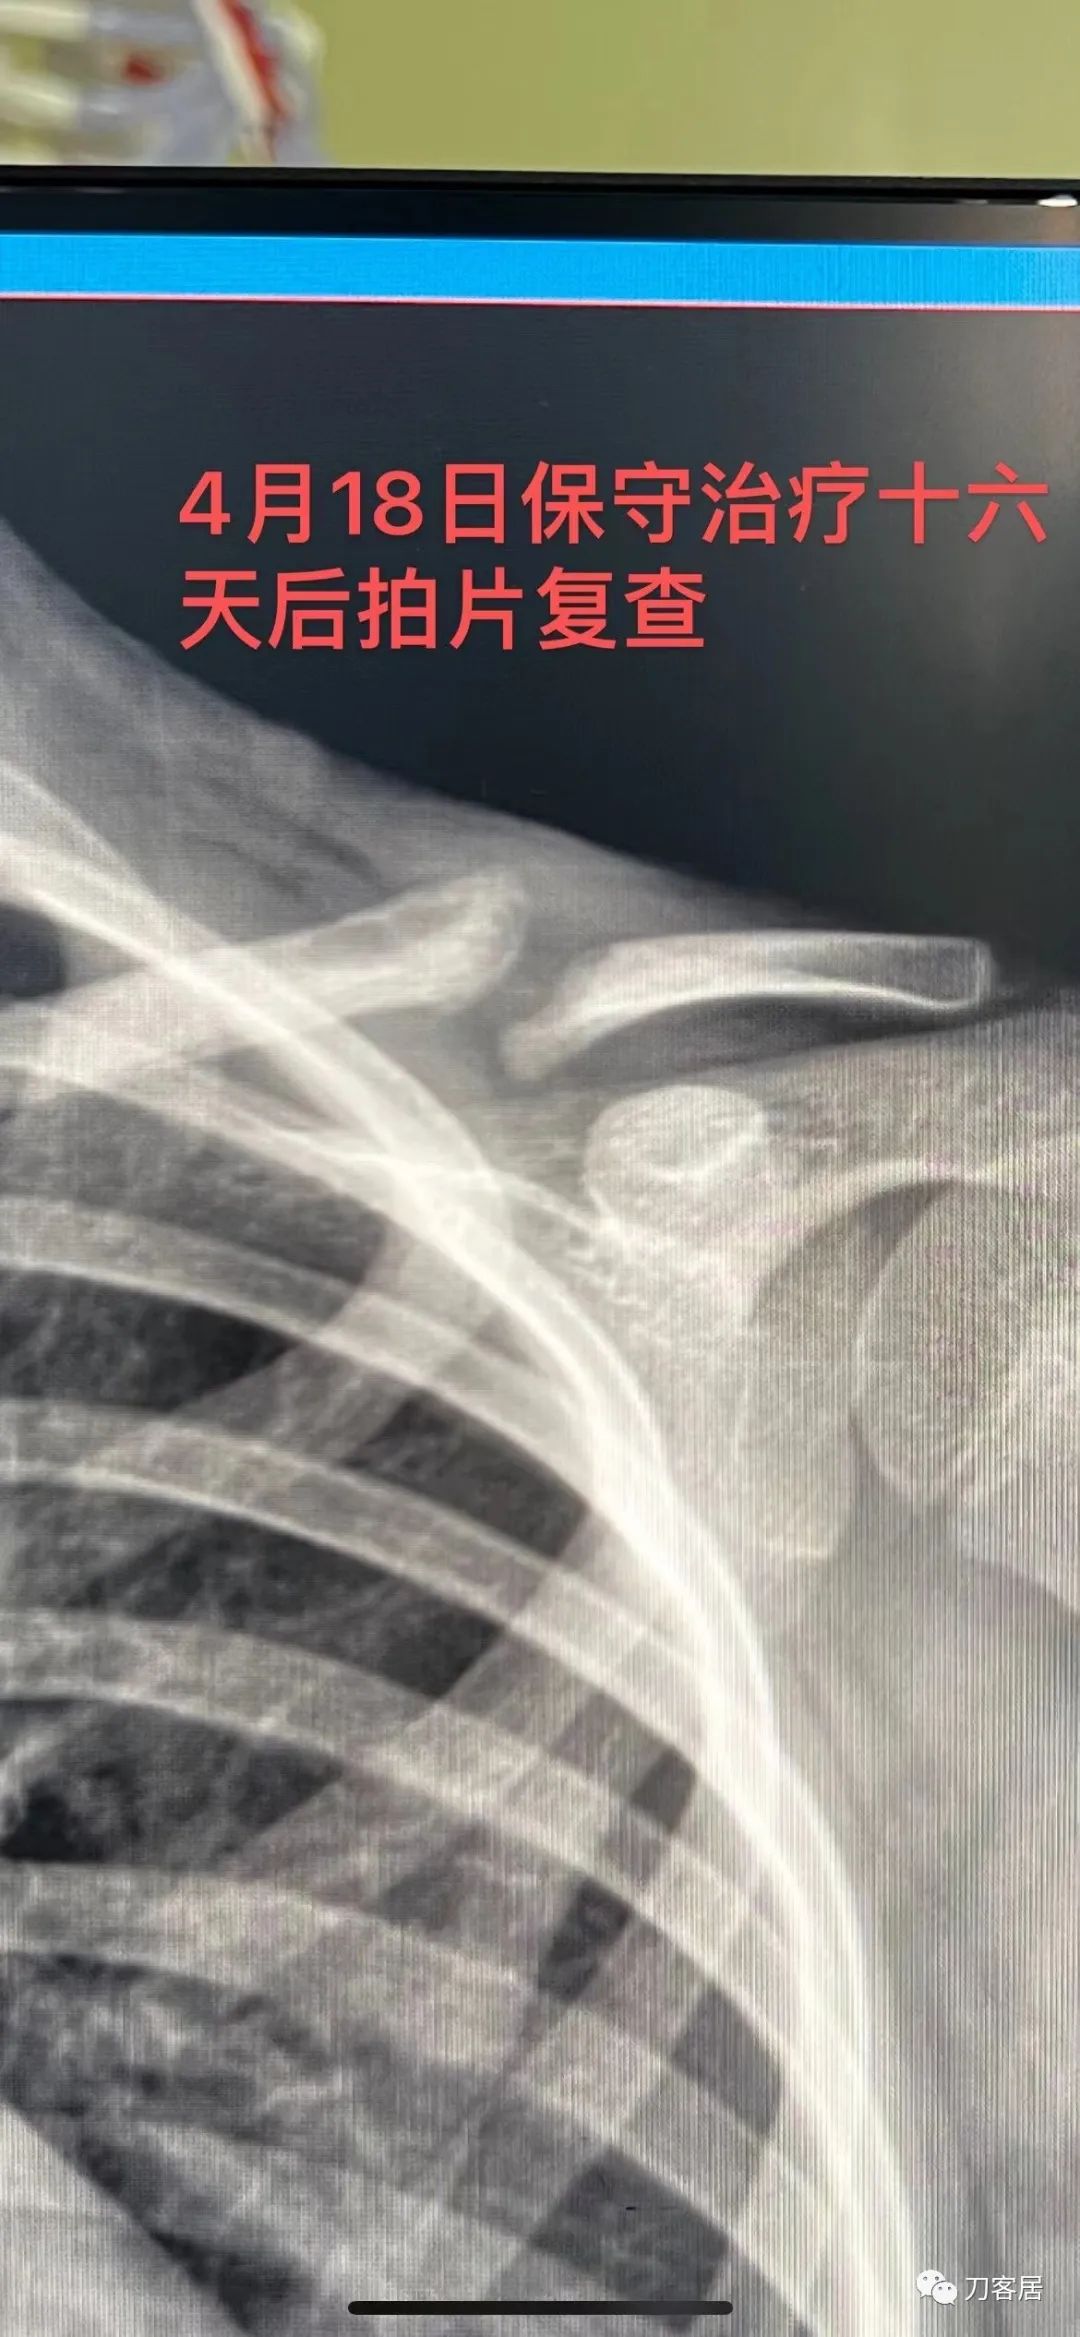

When a non-operative approach is utilized, the fracture is protected for 4-6 weeks, with contact sports avoided for another 6 weeks. As in most simple injuries, half the treatment consists of educating the parents about the normal course. An unsightly lump may appear with fracture healing (callus) and will potentially persist for a year while remodeling progresses (we tell parents that the lump may be the size of a walnut or an egg—Fig.6-7).

当采用非手术方法时,骨折固定 4-6 周,另外6周内避免碰撞运动。与大多数简单的损伤一样,一半的治疗包括对患儿父母进行正常骨折愈合过程的教育。在骨折愈合(骨痂)时可能会出现难看的包块,并且在重塑过程中可能会持续一年(我们应该告诉患儿父母,包块可能有核桃或鸡蛋那么大(图 6-7)。

Although x-rays of a fracture healing in bayonet opposition may frighten the parents, studies have shown that a significant amount of angulation and overlap can be accepted. Once the fracture is non-tender and there is radiographic healing, the patient may slowly return to sports. Final x-rays are usually obtained at 4-6 weeks after injury; if there are concerns of a developing non-union, longer follow-up becomes necessary.

虽然X线片上错位成角骨折愈合可能会吓到患儿父母,但研究表明,较大的成角和重叠可以接受。一旦骨折无痛,且X线片显示有骨愈合,患者可逐渐恢复运动。通常在伤后4-6周行最后一次X线检查;如果存在不愈合可能,则需要更长时间的随访。